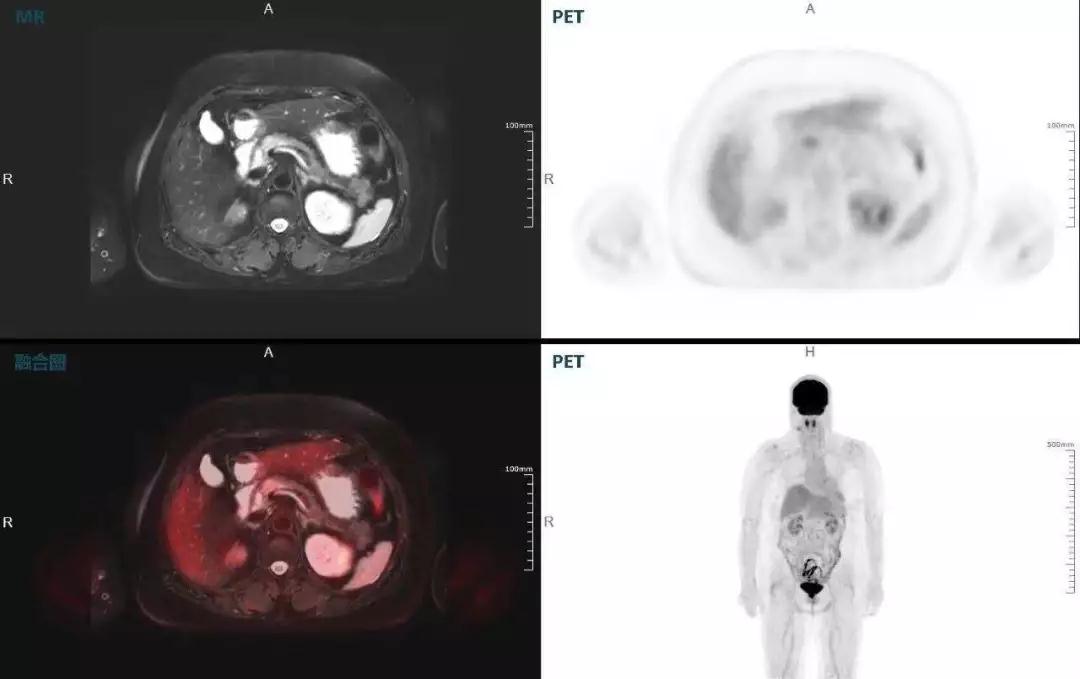

肝癌

聯(lián)影“時空一體”超清TOF PET/MR搭載的壓縮感知技術(shù),能夠同時實現(xiàn)16期成像,精準(zhǔn)捕獲肝臟動態(tài)影像的每一瞬間,同時兼顧早期與晚期等全部期相的完整病灶信息,實時、全方位鎖定病灶。同時,基于其2.8mm超高分辨率,能夠精細(xì)呈現(xiàn)腫瘤邊界信息,捕捉局部微小病灶與遠(yuǎn)端轉(zhuǎn)移灶,助力醫(yī)生精準(zhǔn)診斷。

(對于同一例肝臟惡性腫瘤,PET-CT與PET/MR成像對比??梢钥吹?,聯(lián)影PET/MR圖像對腫瘤邊界和FDG高濃聚區(qū)域清晰顯示。)

胰腺癌

中山醫(yī)院核醫(yī)學(xué)科在臨床實踐中發(fā)現(xiàn),基于聯(lián)影“時空一體”超清TOF PET/MR,不僅解剖信息和代謝信息能夠完美融合呈現(xiàn),同時精細(xì)展示局部病灶與周圍組織的復(fù)雜關(guān)系,并能全盤檢測病灶的全身轉(zhuǎn)移,為醫(yī)生臨床診斷提供更豐富信息。

(胰腺腫瘤,MR顯示胰腺體部信號異常,PET顯示稍高攝取,結(jié)構(gòu)改變和功能異常提示胰腺MT可能大。)